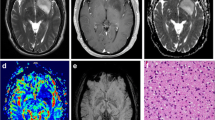

1p/19q co-deleted and non-co-deleted gliomas demonstrated different MR-PET characteristics

Figure 5 shows the MR images (post-contrast T1-weighted image, FLAIR image, MTRasym at 3.0 ppm, and T2 map) and PET images (18F-FDOPA PET) of four patients with different grades and 1p/19q co-deletion statuses as representative examples. Figure 5a shows a newly diagnosed oligodendroglioma patient, with IDH mutation and 1p/19q co-deletion. The tumor was generally homogeneous, with low MTRasym and moderate nFDOPA. The second patient (Fig. 5b) was diagnosed with recurrent anaplastic oligodendroglioma (IDH mutant, 1p/19q co-deleted), with a resection cavity in the left frontal lobe visible in the anatomic MR images. The FLAIR hyperintense lesion ipsilateral to the resection cavity exhibited low MTRasym as well as low nFDOPA. Meanwhile, the lesion on the contralateral side showed high nFDOPA and moderate MTRasym, indicating the existence of active tumor tissue. The voxels in this lesion were situated on the right “tail” part of the scatter plot. Examples shown in both Figs. 5c,d are IDH mutant and 1p/19q non-co-deleted, both characterized by tumor regions with relatively normal nFDOPA but high MTRasym at 3.0 ppm. From these examples, we observed substantially different MR-PET characteristics in 1p/19q co-deleted and non-co-deleted gliomas. Hence, amine CEST and FDOPA may provide complementary information regarding the reprogrammed metabolism of gliomas.

Demonstration of four examples of 1p/19q co-deleted (a,b) and 1p/19q intact (c,d) glioma cases. Each data point in the MTRasym-FDOPA scatter plots represents one voxel in T2 hyperintense lesion. Contours are delineated based on the bivariate histograms of MTRasym and FDOPA, with yellow representing higher and blue representing lower frequency. The regions of interest of gliomas are outlined in red and black in the corresponding MR images.